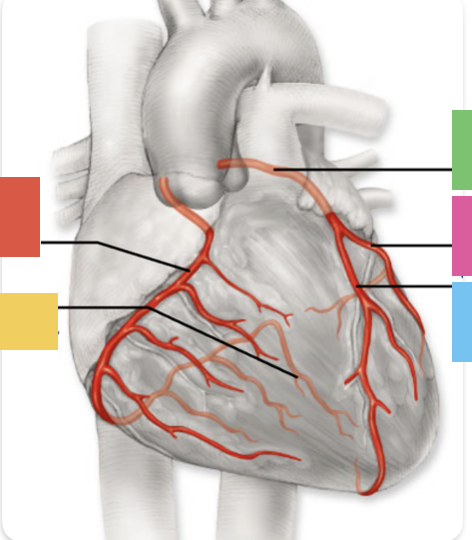

red

right coronary artery

yellow

posterior interventricular artery

green

left coronary artery

blue

anterior interventricular artery

pink

circumflex artery

coronary sinus